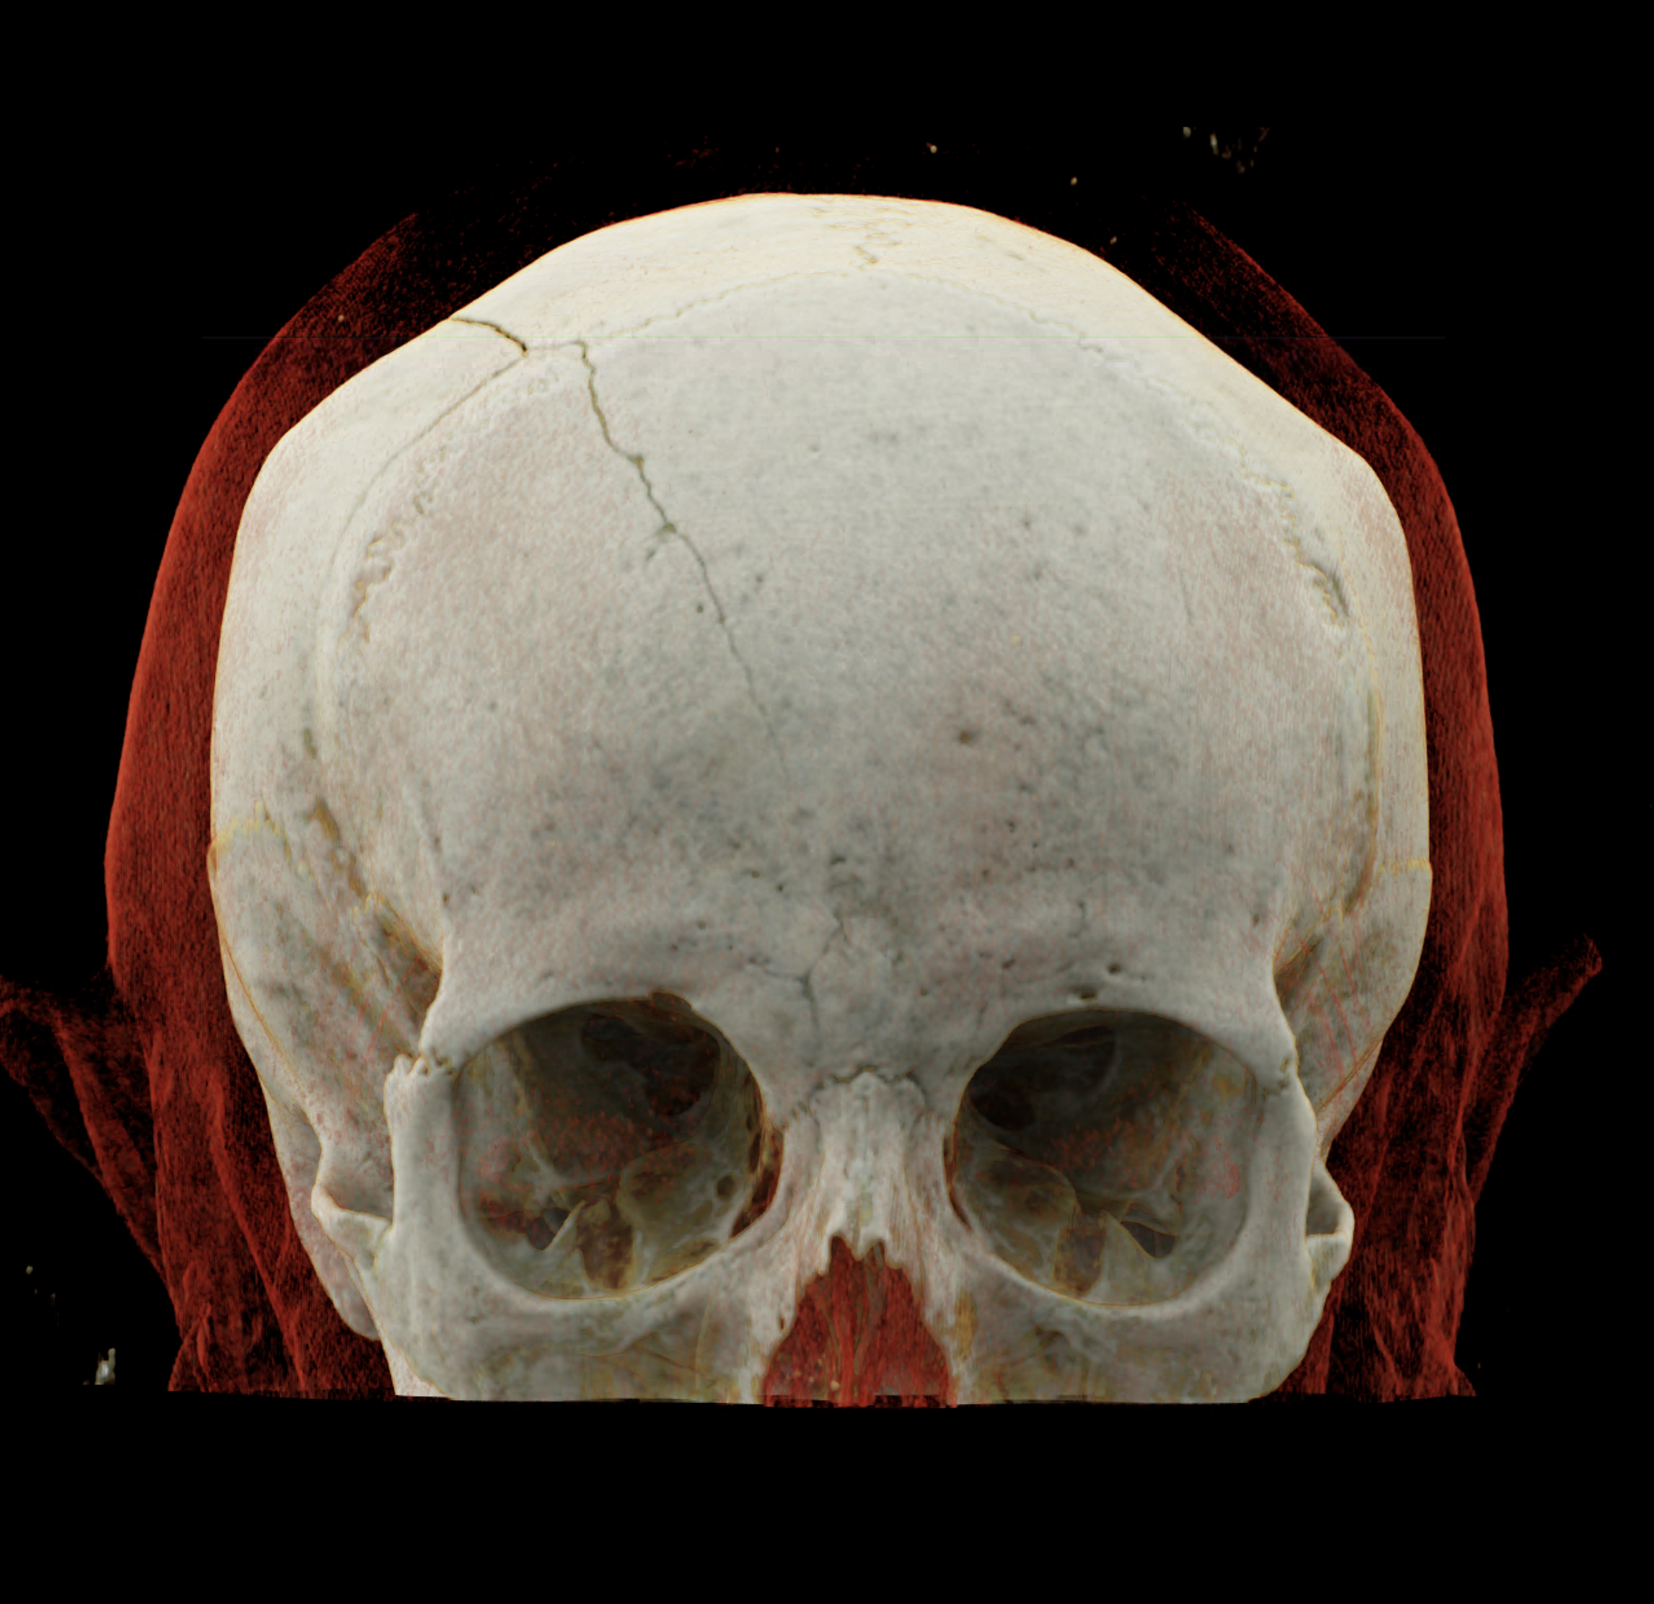

Three-dimensional reconstructions also show a complex skull fissure that extends from the frontal bone to the parietal and temporal bones.

volume rendered technique – display of the fissure course